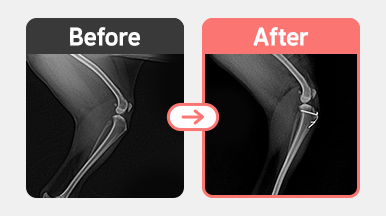

진단명 : 양측 슬개골 탈구 / 우측 G2 좌측 G3

우측 2기 : 대퇴고랑성형 + 경골조면 이식

우측은 무릎 홈이 얕아 슬개골이 쉽게 빠지는 상태로, 대퇴고랑성형(trochleoplasty) 과 경골조면 이식(TTT)을 통해 정렬을 교정하였습니다.